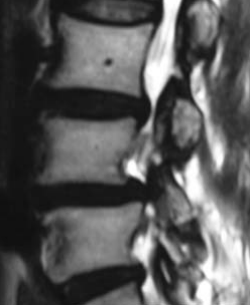

IMAGING STUDIES

Has imaging studies showed grade 1 degenerative spondylolisthesis L45 with moderately severe subarticular and subarticular stenosis at L5S1 and L34.